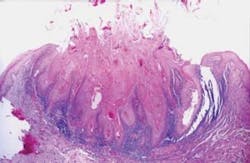

The first reported case of oral bisphosphonate-induced necrosis involved the administration of Fosamax and the subsequent failure of five fully integrated dental implants.2 In 2003, another case report surfaced and osteonecrosis was reported after intravenous administration of bisphosphonates during cancer treatment.2

Since then, a growing number of case reports and cohort studies have been published that have linked bisphosphonate therapy and osteonecrosis of the jaws (ONJ). In 2011, a case control study revealed that bisphosphonate use was strongly associated with ONJ for intravenous use and less so for oral use.3 Risk markers included local suppuration, dental extraction, and radiation therapy.3 When cancer patients were excluded, bisphosphonate use, suppuration, and extractions remained associated with ONJ.3 Higher risk of ONJ began within two years of bisphosphonate initiation and increased fourfold after two years for both IV and oral bisphosphonates. Suppuration and dental extractions were identified as independent risk factors for ONJ.3

The use of the term “bisphosphonate-associated osteonecrosis of the jaw” or BON/BRONJ has now been replaced by the term ARONJ which stands for “antiresorptive agent-induced ONJ.” According to the ADA, the reason for the change in terminology is because there are some non-bisphosphonate agents now available for treatment of women with postmenopausal osteoporosis and cancer patients that could also end up being associated with ONJ.4 Time and more research data will eventually tell the whole story.